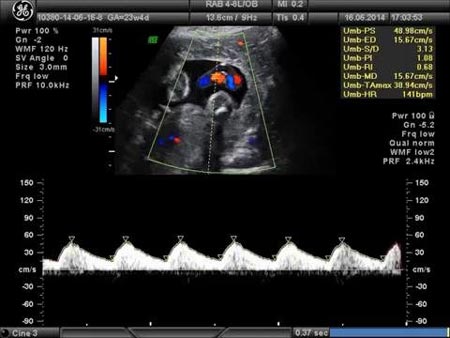

ضربان قلب نرمال جنین معمولا بین 120 تا 160 ضربه در دقیقه در دوران بارداری است اما در اوایل سه ماهه اول، ضربان قلب جنین کندتر است. بطور متوسط ضربان قلب جنین بین هفته های هفت تا هشت بارداری در سونوگرافی مشخص میشود. در ابتدا ضربان قلب پایین و سپس تا هفته 10 بارداری افزایش می یابد و شاید به 170 ضربه در دقیقه هم برسد اما بعد از آن ضربان قلب جنین کاهش یافته و به 130 ضربه در دقیقه هم می رسد. مطالعه ای در سال 1996 نتایج زیر را به عنوان حداقل ضربان قلب طبیعی در سونوگرافی های بارداری اولیه اندازه گیری کرد، که اندازه آن با توجه به قطب جنین متفاوت بود:

- نطفه 2 میلیمتری: 75 ضربه در دقیقه

- نطفه 5 میلیمتری: 100 ضربه در دقیقه

- نطفه 10 میلیمتری: 120 ضربه در دقیقه

- نطفه 15 میلیمتری: 130 ضربه در دقیقه